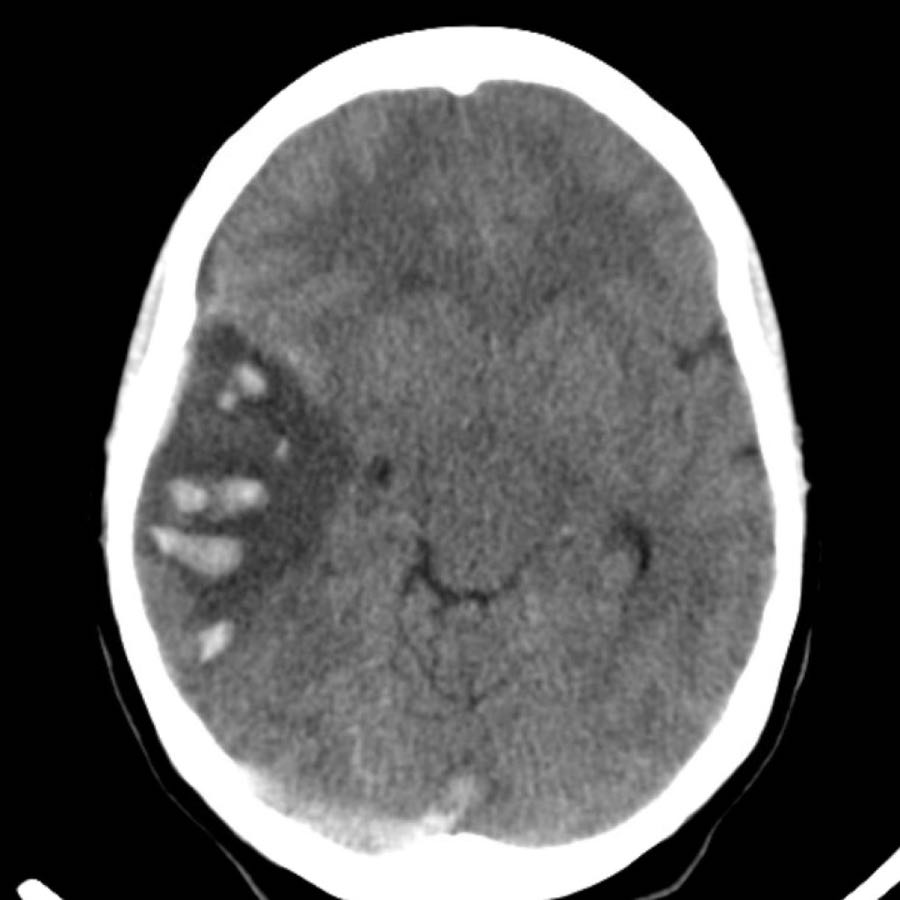

Ba hình ảnh đầu tiên cho thấy khối tụ máu lớn tại hạch nền bên phải kèm phù não lan rộng.

Hình ảnh theo dõi một năm sau cho thấy hình ảnh hang hóa dạng tuyến tính do mất mô (mũi tên) và giảm tỷ trọng hạch nền là hậu quả của xơ hóa thần kinh đệm (gliosis).